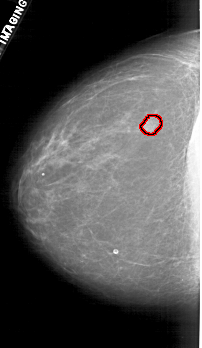

A_1880_1.LEFT_CC

LEFT_CC LINES 4516 PIXELS_PER_LINE 2626 BITS_PER_PIXEL 12 RESOLUTION 43.5 OVERLAY

FILE: A_1880_1.LEFT_CC.OVERLAY

TOTAL_ABNORMALITIES 1

ABNORMALITY 1

LESION_TYPE MASS SHAPE LOBULATED MARGINS OBSCURED

ASSESSMENT 4

SUBTLETY 5

PATHOLOGY BENIGN

TOTAL_OUTLINES 1

BOUNDARY